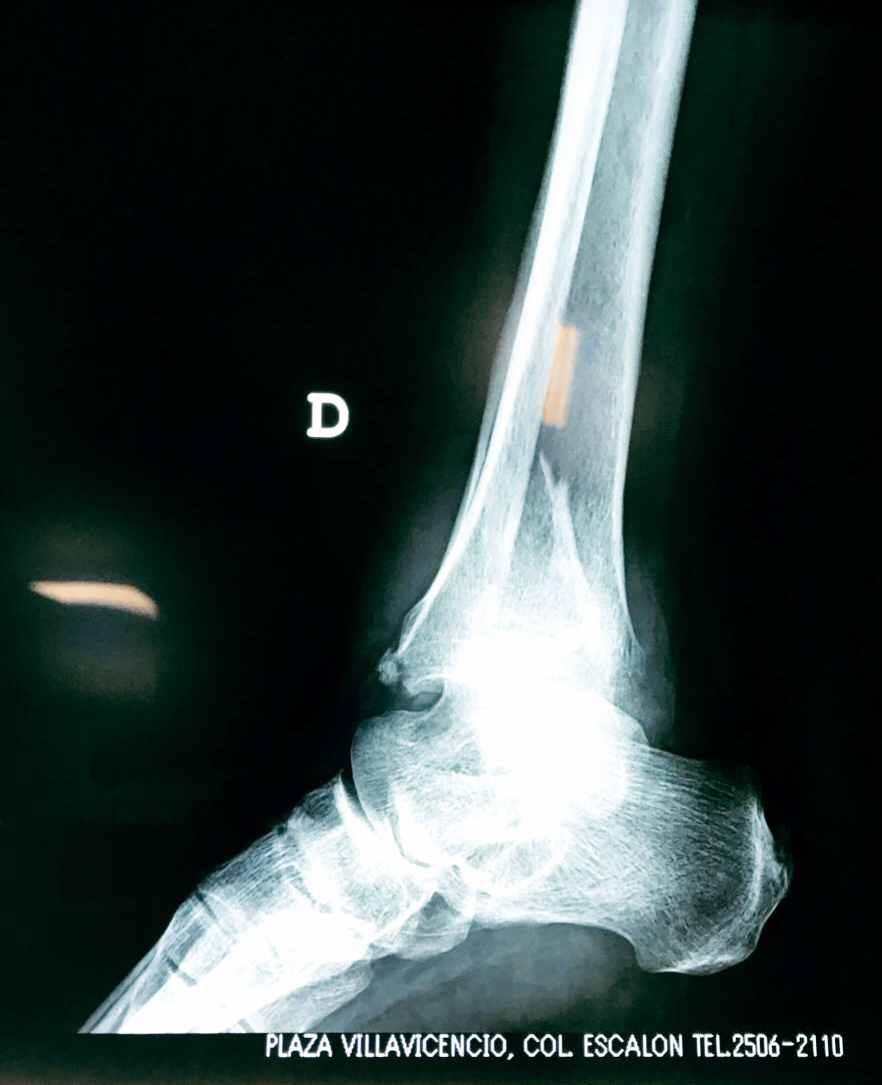

Una fractura de tobillo es la rotura de uno o más de los huesos del tobillo. Estas fracturas pueden ser:

- Los extremos de los huesos están desalineados entre sí (desplazados).

- La fractura se extiende hasta la articulación del tobillo (fractura intra-articular).

- Los tendones o ligamentos (tejidos que sujetan los músculos y los huesos entre sí) están rotos.